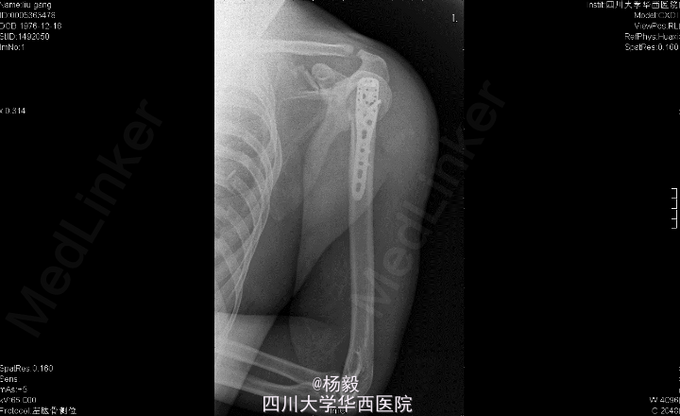

男,33岁11月,因“车祸伤后全身多处疼痛、左上肢活动障碍9小时”入院。 患者自述入院前9小时,被货车撞伤,具体受伤姿势及着力方式不清,患者原发昏迷约5分钟,醒后能回忆受伤情况,患者述胸部及左肩部疼痛,呼吸困难,气促,左上肢感觉麻木,左手伸屈活动受限,患者无恶心呕吐,无咯血,感腹部稍微疼痛,无大小便失禁,其余四肢无活动障碍,曾经当地医院诊治,具体诊断不详,行对症治疗后,患者感呼吸困难加重,为进一步治疗,患者转我院,门诊请胸科会诊后行左侧胸腔闭式引流术,请普外科会诊后,认为腹部无明显指征,暂观察,急诊以“左肩胛骨骨折,左肱骨外科颈骨折,胸腔积液'收住我科。

胸廓左侧胸廓呼吸动度减弱,左胸部腋中线处见一闭式引流管接水封瓶。,双肺叩诊呈清音,双肺呼吸音清,未闻及干湿啰音及胸膜摩擦音。腹部外形正常,全腹柔软,上腹压痛,无反跳痛,腹部未触及包块,肝脏肋下未触及,脾脏肋下未触及,双肾未触及。双下肢无水肿。专科检查:视:左上臂夹板外固定,解开夹板后见左肩部及左上臂肿胀,左上臂下段外侧见约5cm*8cm皮肤擦伤。触:左肩胛部及左肩部压痛,左前臂下段 以远痛温触觉较对侧减退,左桡动脉能扪及,左手甲床微循环正常。动量:左肩关节、左肘关节、左腕关节及左手指各关节伸屈活动受限。 辅助检查:X片检查示:左肩胛骨及左肱骨上段骨折,左侧多发肋骨骨折,左肺挫伤,左胸腔积液,脾区高密度影。

初步诊断:1、左肩胛骨粉碎性骨折。2、左肱骨外科颈骨折伴神经损伤。3、左侧胸腔积液闭式引流术后。4、左侧多发肋骨骨折。5、左肺挫伤。6、脾脾脏损伤? 全麻下行左肱骨外科颈骨折切开复位内固定术。